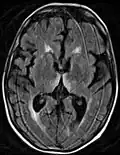

Axial MRI FLAIR image showing hyperintense signal in the mesial dorsal thalami, a common finding in Wernicke encephalopathy. This patient was nearly in coma when IV thiamine was started, he responded moderately well but was left with some Korsakoff type deficits.

Axial MRI B=1000 DWI image showing hyperintense signal indicative of restricted diffusion in the mesial dorsal thalami

Axial MRI FLAIR image showing hyperintense signal in the periaqueductal gray matter and tectum of the dorsal midbrain